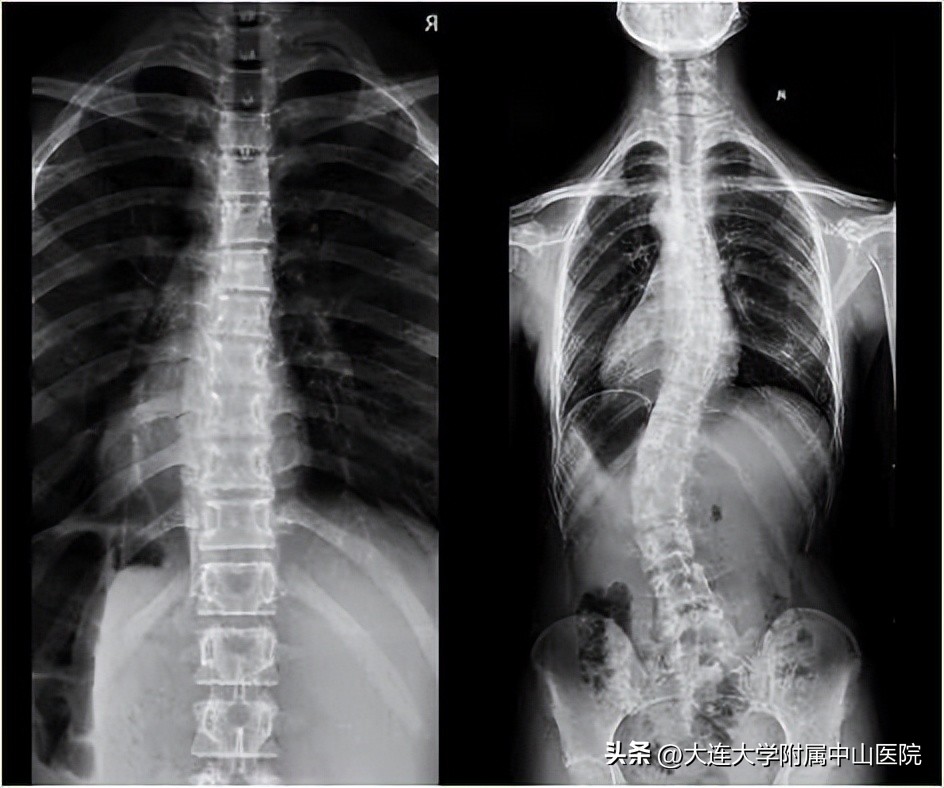

脊柱侧弯已经和近视、肥胖、心理疾病并列成为我国青少年体质健康的四大主要问题。发病率逐年升高,并且逐渐低龄化。目前我国中小学生脊柱侧弯人数预计超过500万,并且还在以每年30万左右的速度递增。

简单的理解,就是原本应该竖直的脊柱由于种种原因向两侧弯曲而产生的脊柱畸形。目前在青少年及儿童中发病率已高达10%左右。

脊柱侧弯会对青少年的健康造成严重影响,一旦出现如不治疗,就会不断加重,首先会严重影响儿童及青少年的生长发育,造成身体变形,严重影响日常生活、美观及孩子心理健康。严重者则会影响到心肺功能,甚至造成瘫痪。